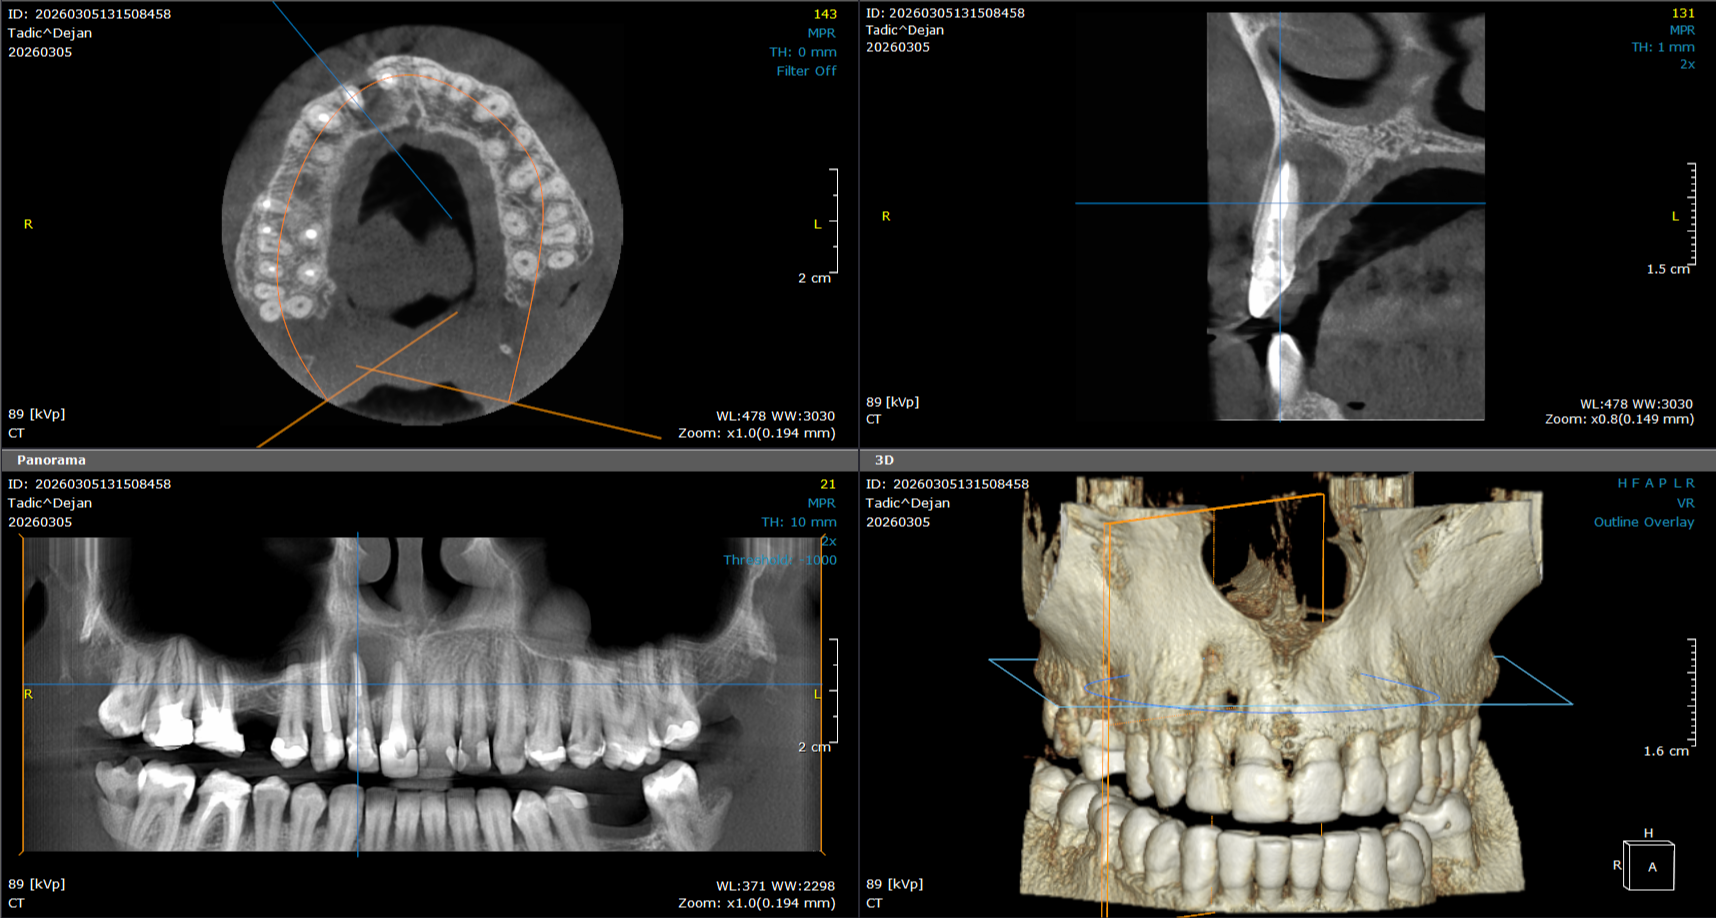

3D snimanje zuba predstavlja savremenu dijagnostičku metodu u stomatologiji koja omogućava trodimenzionalni prikaz zuba, vilice i okolnih anatomskih struktura. Ova tehnologija, poznata kao CBCT (Cone Beam Computed Tomography), pruža izuzetno precizne informacije koje stomatolozima pomažu u planiranju terapije i izvođenju složenih stomatoloških procedura.

Za razliku od klasičnih 2D snimaka, 3D snimci omogućavaju detaljan prikaz kosti, položaja zuba, nervnih kanala i sinusa, što je posebno važno kod planiranja ugradnje implantata, ortodontske terapije, endodontskog lečenja i hirurških intervencija.

3D snimak – CBCT preporučuje se u situacijama kada je potrebno dobiti detaljan prikaz zuba, kosti i okolnih struktura. Zahvaljujući visokoj preciznosti CBCT tehnologije, stomatolozi mogu tačno proceniti stanje i planirati optimalnu terapiju.

3D snimanje omogućava preciznu procenu količine i kvaliteta kosti, kao i tačno određivanje pozicije implantata.

Detaljan prikaz položaja zuba i vilica pomaže ortodontima u planiranju terapije i praćenju razvoja zuba.

3D snimak omogućava precizno određivanje položaja impaktiranih umnjaka i odnosa sa nervima.

Kod komplikovanih slučajeva lečenja zuba, 3D snimanje pruža detaljan uvid u strukturu korena.

3D dijagnostika omogućava rano otkrivanje promena koje se ne vide na standardnim snimcima.

Jedna od najvećih prednosti 3D snimanja zuba je izuzetna preciznost i mogućnost analize svakog detalja. Za razliku od tradicionalnih 2D snimaka, gde se strukture preklapaju, 3D tehnologija omogućava slojevito prikazivanje zuba, kostiju i okolnih anatomskih struktura.

To znači da stomatolog može jasno da vidi položaj živaca, debljinu kosti i potencijalne komplikacije pre same intervencije. Na taj način se smanjuje rizik i povećava sigurnost svakog zahvata, posebno kada je u pitanju ugradnja implantata ili složeniji hirurški zahvati.